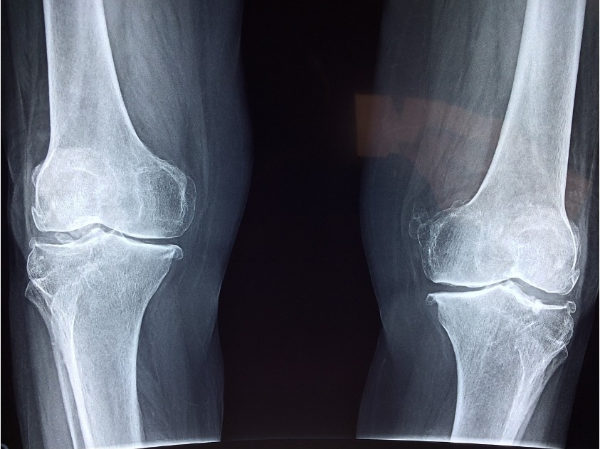

골다공증이란 무엇일까요? 골다공증은 골격의 밀도와 질이 감소하여 골절의 위험이 증가하는 질환입니다. 골다공증은 초기에는 특별한 증상이 없다가 뼈가 골절되고 나서야 알게 되는 경우가 많아서 '소리 없는 도둑’이라는 별명이 붙기도 했습니다. 골다공증은 나이가 들면서 자연스럽게 발생할 수 있지만, 여러 가지 원인으로 인해 조기에 발생하거나 악화될 수도 있습니다. 골다공증의 원인은 크게 세 가지로 나눌 수 있습니다.